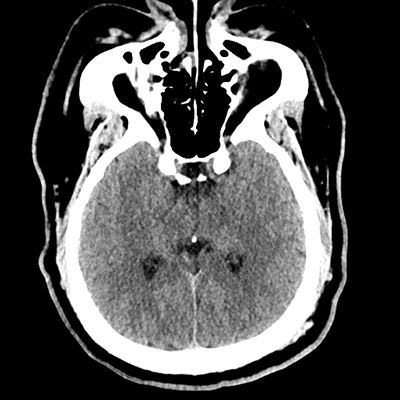

NCHCT

NCHCT 2/16 2/16